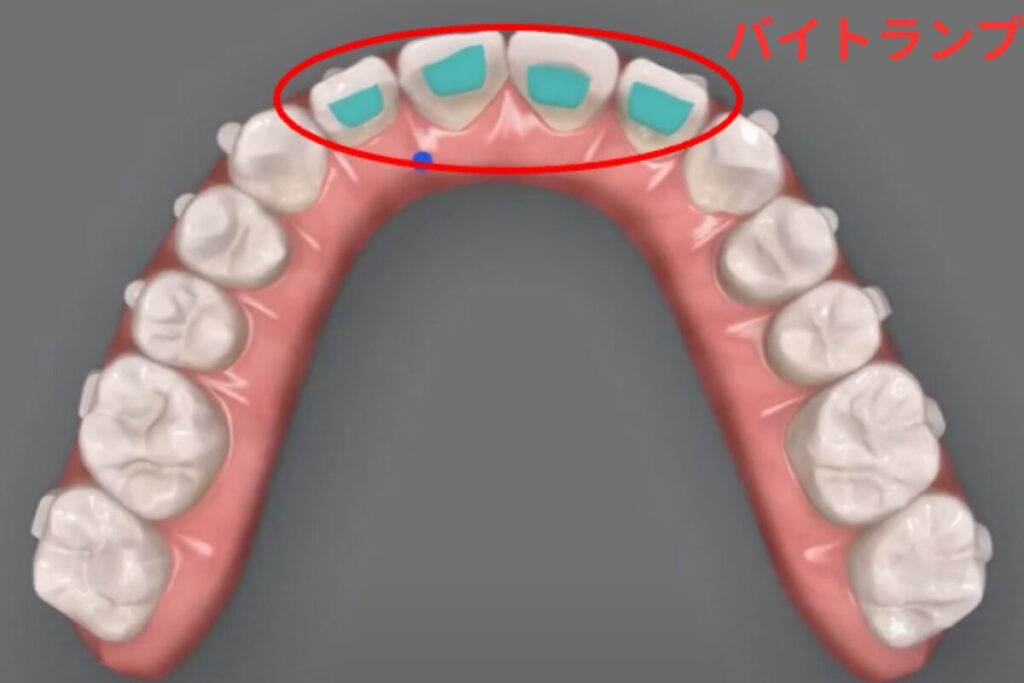

最新のインビザラインでは「バイトランプ」という特殊な突起を取りつけることで、噛む力を利用して前歯の深い噛み込みを改善することができたりします。

最新のインビザライン(G8システム以降)は、バイトランプやスマートフォースといった機能により、以前よりも奥歯の挺出や歯の角度コントロールが得意になりました。

特に、過蓋咬合や前歯の角度が原因の場合は、バイトランプ機能や様々な工夫により効果的な改善が可能です。

特に、過蓋咬合や前歯の角度が原因のガミースマイルには、最新のG8システムが効果を発揮することがあります。